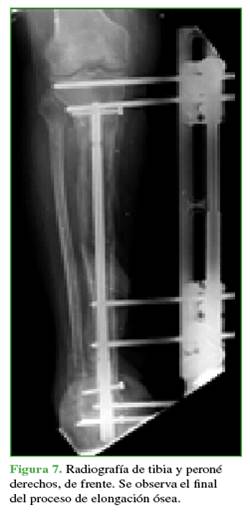

Una vez completado el transporte óseo, los pacientes pasan a la etapa de compresión del sitio de acoplamiento (Figuras 7 y 8). Esto se llevó a cabo mediante el sistema de transporte o la compresión con una placa de compresión dinámica sin invadir el foco (Figura 9).